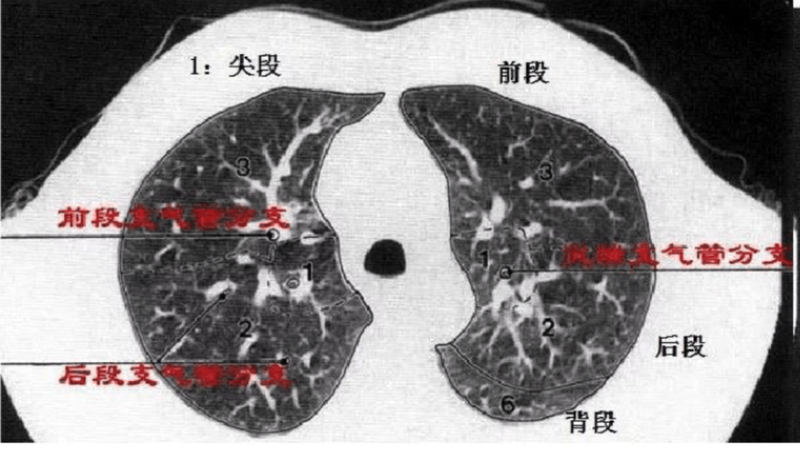

上叶:S1:尖段;S2∶后段;S3:前段。